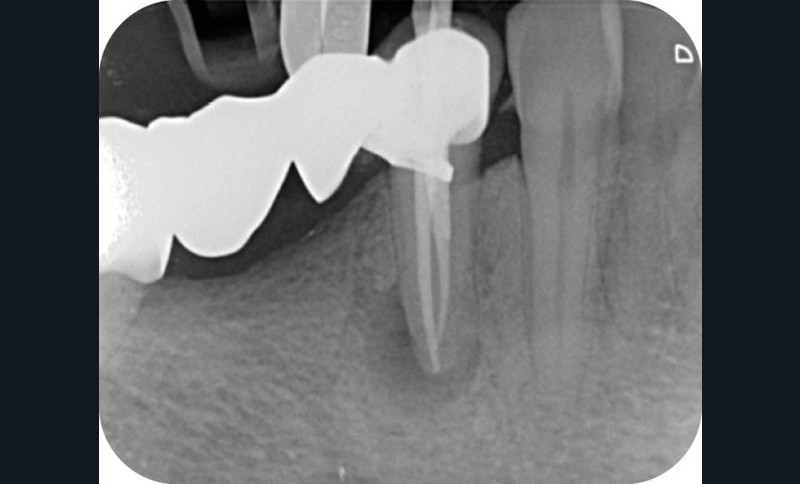

La cavité d’accès endodontique était alors traditionnellement réalisée en se figurant les axes de la racine et du bridge (fig. 2). Cette aptitude à s’orienter dans l’espace n’est cependant pas aisée, et différents outils numériques offrent aujourd’hui la possibilité de dessiner la trajectoire suspectée du canal sur les coupes de l’examen Cone Beam et d’aider le praticien à planifier son futur geste thérapeutique (fig. 3, 4). Après pose du champ opératoire, une voie d’accès est ainsi réalisée à travers le bridge en reportant les mesures de la planification 3D (fig. 5). Le tenon est déposé par vibration avec un insert ultrasonore puis la lecture des teintes dentinaires sous microscope permet d’objectiver la présence d’un canal supplémentaire non traité (fig. 6). Les surplombs dentinaires sont supprimés avec un insert ET18D (Actéon) et les entrées canalaires relocalisées avec une lime rotative d’évasement coronaire.

La mise en forme canalaire à travers un bridge impose des contraintes instrumentales importantes, et nécessite une analyse préopératoire minutieuse. Ici, nous avons eu recours à des limes de pré-élargissement mécanisé afin de sécuriser la trajectoire canalaire (fig. 7). Une préparation corono-apicale jusqu’à une finition apicale 25-6 % a ensuite été choisie afin d’optimiser le flux d’irrigant dans le tiers apical. À la suite de l’ajustage des maîtres cônes et d’un protocole d’irrigation finale (EDTA & NaOCl), une obturation selon la technique de condensation verticale à chaud est réalisée, puis la patiente est revue pour une restauration composite de la face occlusale (fig. 8, 9). Le contrôle à six mois révèle la disparition de la symptomatologie ainsi que des signes radiologiques de cicatrisation apicale (fig. 10).